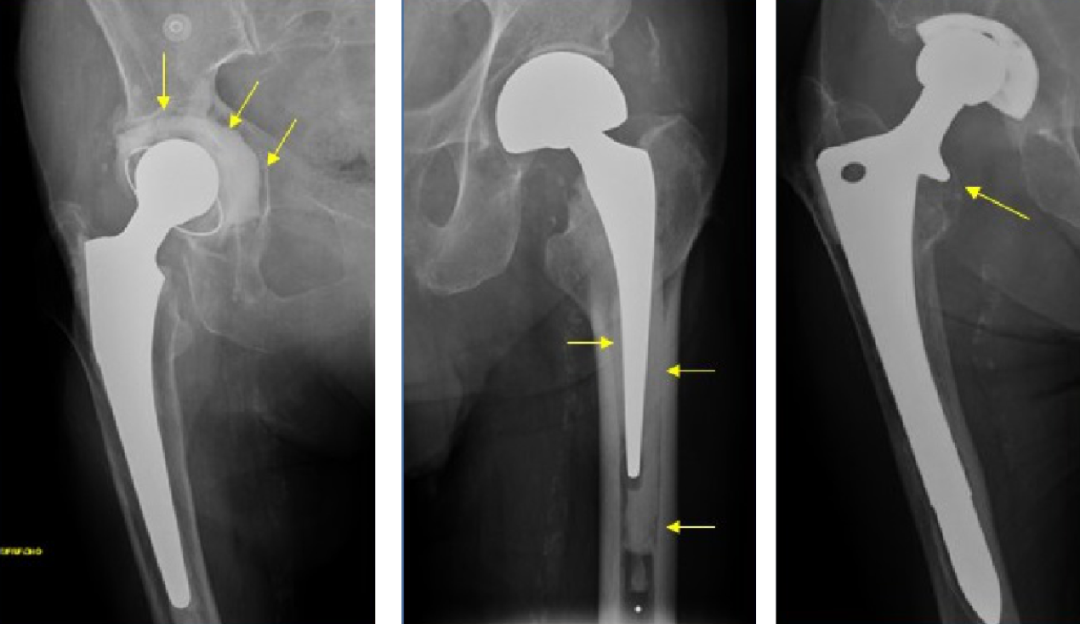

5. Metal-on-metal(MOM)disease:

假性滑囊,是金属对金属髋关节置换的组织反应;表现为髋关节假体周围的滑囊。最常见的部位是:髋臼上缘、大粗隆和小粗隆。

人工髋关节置换术。假体周围囊性肿块(箭头)